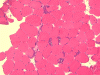

Pathology of the case: On hematoxylin-eosin stained frozen sections, there are many stongly basophilic, irregular subsarcolemmal depositions (Panel A and B). There is no significant variation in fiber diameter, increase in centrally located nucleus, inflammation, necrotic fiber, regenerating fibers or target fibers. These deposits appear bright red on modified Gomori's trichrome (Panel C). On ATPase reaction at pH 4.6 (dark fibers are type 1, pale fibers are type 2a while intermediate-intensity fibers are type 2b), there is no fiber type predominance (Panel D). Although the deposits are not visualized in the ATPase preparation, they are strongly reactive in NADH-TR reaction. Intesestingly, these deposits are not visualized in another preparation of oxidative enzyme- succinate dehydrogenase (Panel F). On the adenylate deaminase preparation, these deposits are strongly reactive (Panel G). The subsarcolemmal deposits are well visualized under the electron microscope which is electron dense (Panel H). On cross sections, these deposits are bundles of densely packed polygonal to round tubules with double walls that are arranged in small fascicles (Panel  I and J). The tubules are about 50-80 nm in diameter. The tubular aggregates also arrange in longitudinal bundles that run along the myofibrils (Panel K).

Tubular aggregates are well demonstrated in many routinely used histochemical stain. In general, tubular aggregates appear as irregular, subsarcolemmal depositions 4. They appear bright red in modified Gomori's trichrome. These aggregates appear strongly basophilic on hematoxylin-eosin stained frozen sections but they are quite indistinctive in paraffin embedded sections stained with hematoxylin-eosin. The aggregates appear intensely dark blue on NADH-TR reactions and this feature lead to the early impression that they are derived from the mitochondria. However, their lack of succinate dehydrogenase. Tubular aggregates are also strongly positive for lactate dehydrogenase and adenylate deaminase. These features argue against a mitochondrial origin.  Tubular aggregates are usually but not invariably found in type II fibers.